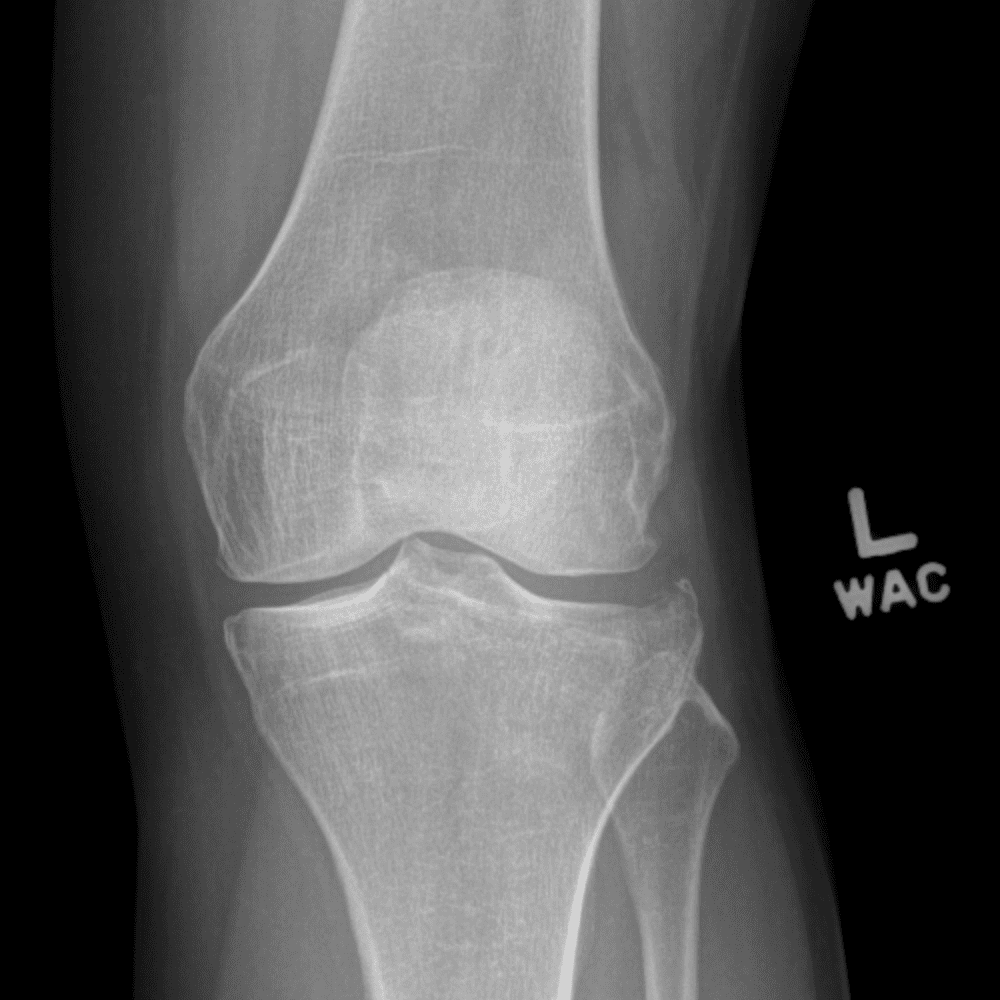

Simula o plantão incluindo casos sutis ou difíceis e alguns normais.